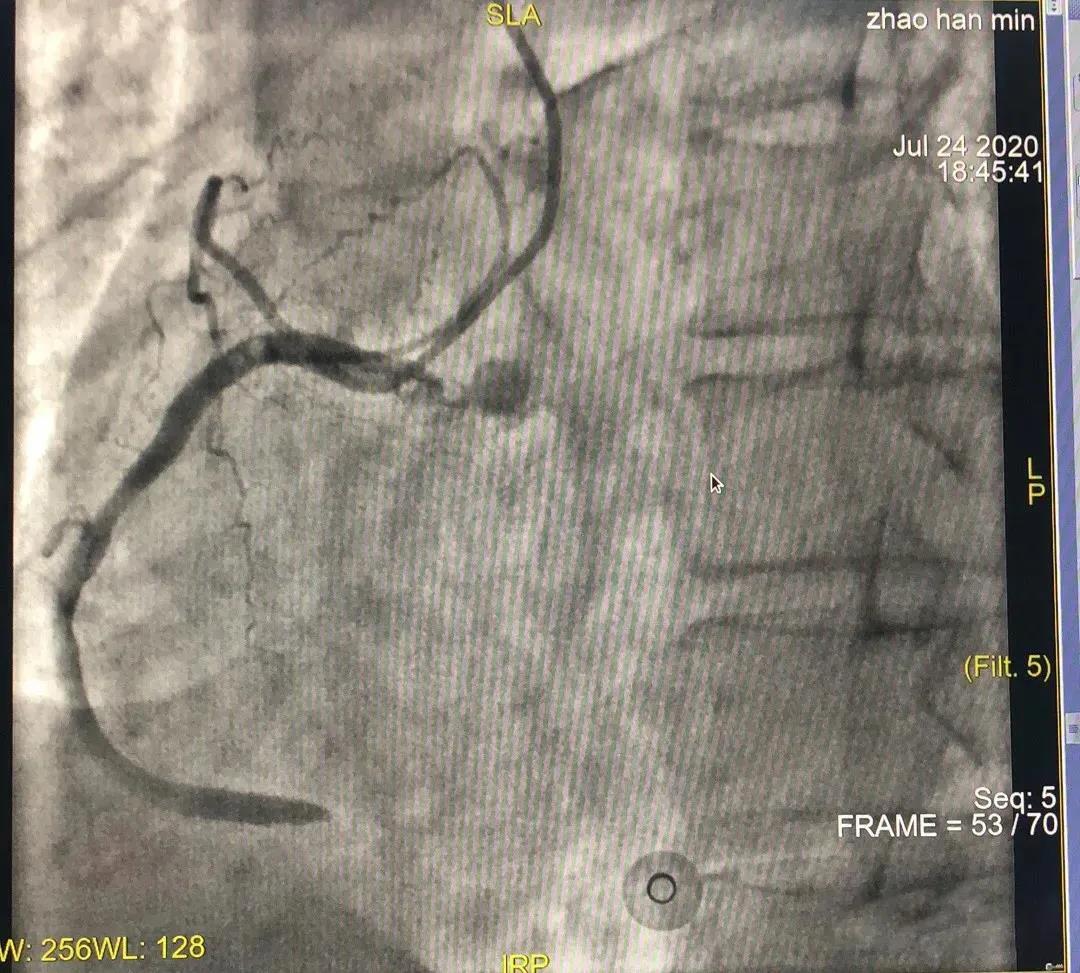

胸痛优先!确诊为STEMI的患者,需要紧急救治。患者迅速转移至导管室,很快就完成了冠状动脉造影检查:

上图:右冠状动脉造影检查,提示血管急性闭塞

冠状动脉造影检查提示:右冠状动脉急性闭塞。其下游被其供血区域的心肌发生缺血坏死;患者出现胸闷胸痛出汗,严重者甚至还会发生休克、心脏停跳以及心室颤动等;心电图也出现了相应的改变,这就是急性ST段抬高型心肌梗死(STEMI)的典型表现。